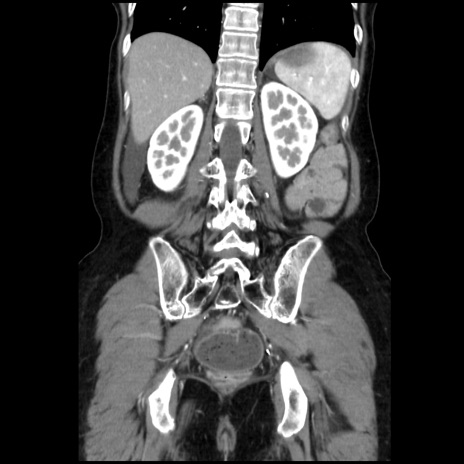

症例32(冠状断像)

【症例】40歳代 女性

【主訴】上腹部痛、嘔気・嘔吐

【現病歴】約9時間前頃から急に上腹部痛、嘔気、嘔吐が出現。改善しないため救急要請。

【既往歴】子宮頚癌(広汎子宮全摘術、放射線療法)、腸閉塞

【身体所見】腹部:平坦、軟、腸雑音亢進、上腹部を中心に腹部全体に圧痛あり。

【データ】WBC 8400、CRP 0.03